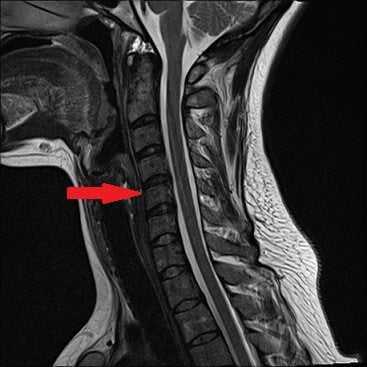

Диагноз выставляется на основании внешнего и неврологического осмотра, данных анамнеза. Во время проведения беседы на первом приеме врач просит больного описать характер головокружений. Для подтверждения диагноза проводится ряд инструментальных исследований:

- МРТ или КТ для оценки состояния дисков, кровеносных сосудов, нервных стволов, мягких тканей;

- сформировавшиеся остеофиты (острые костные наросты) сдавливают позвоночную артерию, что приводит к снижению объема крови, поступающей в головной мозг;

- позвонки и диски утрачивают стабильность, поэтому происходят подвывихи верхних суставных отростков, а просвет кровеносных сосудов уменьшается;